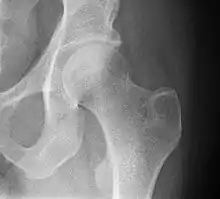

Radiograph of a healthy human hip joint

The hip joint is a ball and socket synovial joint formed by the articulation of the rounded head of the femur and the cup-like acetabulum of the pelvis.[5] The socket of the acetabulum is pointing downwards and anterolaterally. The socket is also turned such that the outer edge of its roof is more lateral than outer edge of the floor.[5] It forms the primary connection between the bones of the lower limb and the axial skeleton of the trunk and pelvis. Both joint surfaces are covered with a strong but lubricated layer called articular hyaline cartilage.